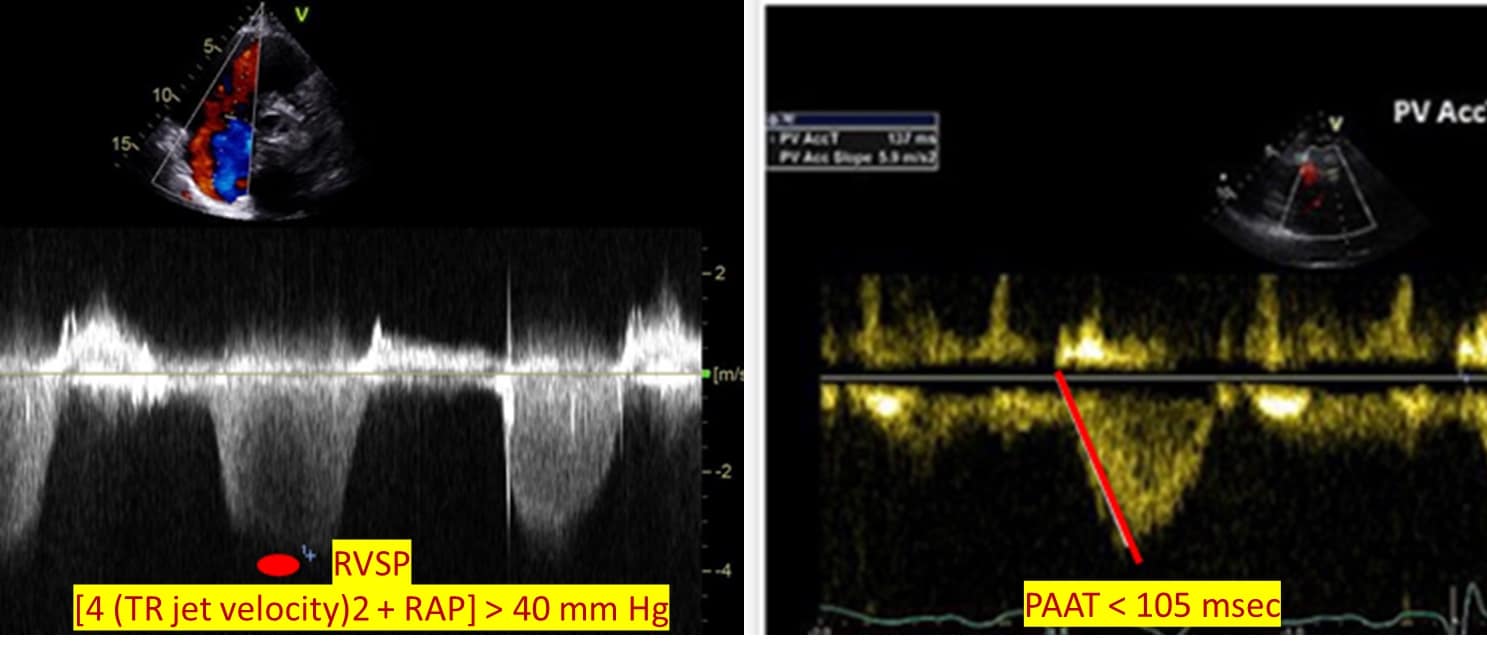

Another important assessment that can be performed with an echocardiogram is pulmonary hemodynamics. Right ventricular systolic pressure is calculated by applying the simplified Bernoulli equation to TR jet velocity and added to right atrial pressure [4 (TR jet velocity)2 + RAP]. Right ventricular outflow tract (RVOT) velocity time integral (VTI) is increasingly being used to characterize pulmonary vascular resistance (PVR). The normal RVOT VTI jet has a parabolic velocity curve with a delayed onset to peak flow. As PVR increases, the flow peaks earlier.11,19 Lastly, while pressure-volume loop measurement is the gold standard for RV-pulmonary artery coupling measurements, TAPSE/PASP is increasingly used as a surrogate. A variety of cutoffs for TAPSE/PASP are reported throughout the literature and vary depending on the patient population.20 (Figure 6)

Figure 6: RV-PA hemodynamic assessment.

RVSP = right ventricular systolic pressure, TR = tricuspid regurgitant, RAP = right atrial pressure, PAAT = pulmonary artery acceleration time